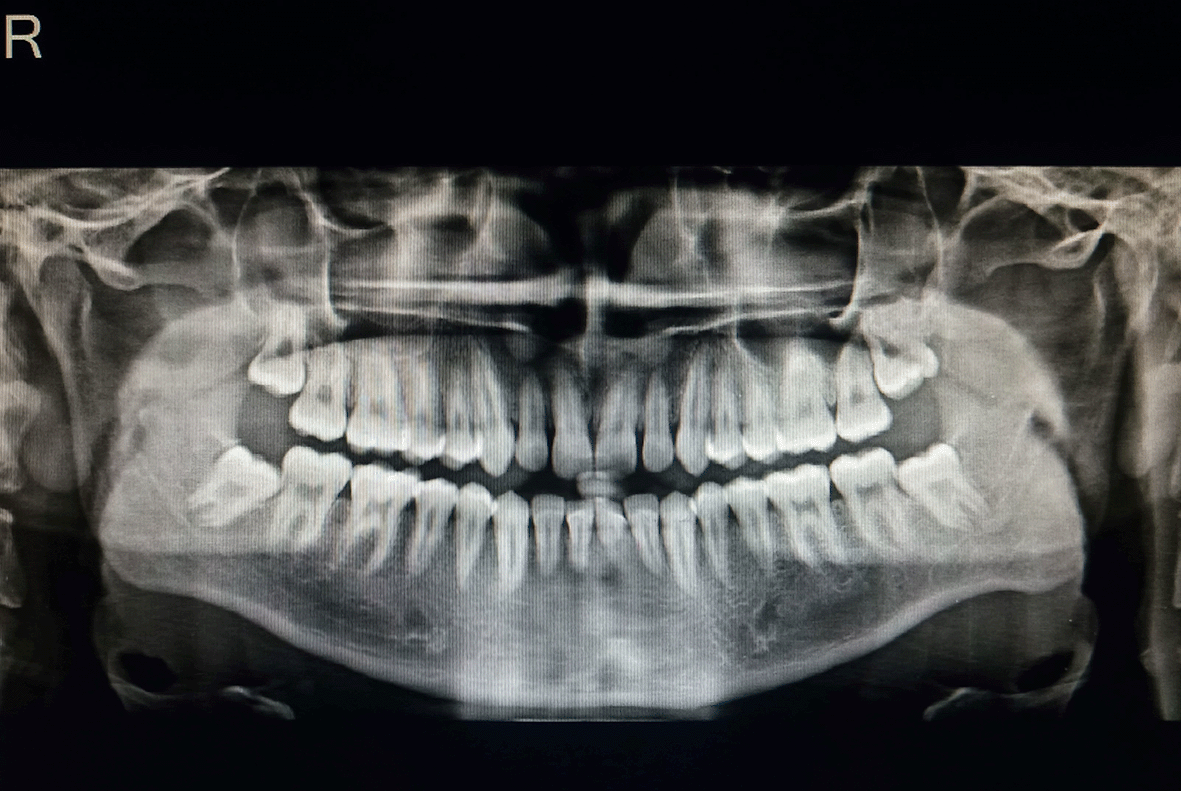

An orthopantomogram (OPG) was performed to look for any pathology (Figure 3). Compared to the right side, the antagonial notch on the OPG scans was slightly more pronounced. Other anomalies were not found in OPG.